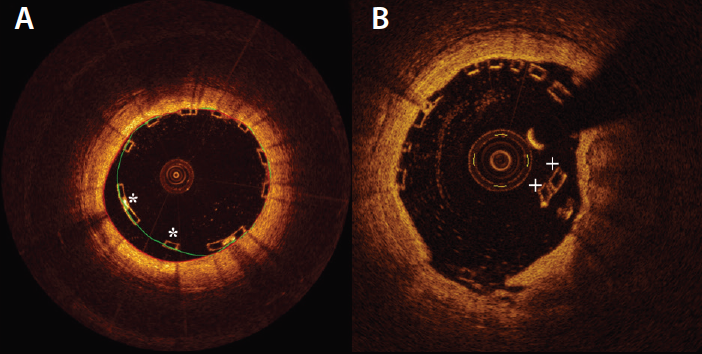

Compared to DESs, BRSs have a limited range of expansion (ie, 0.5 mm more than the reference diameter) due to their polymeric composition, limiting their use in cases of vessel tapering (Table 2). Huge malapposition can be uncorrectable and persist at follow-up until resorption occurs, and attempts to correct large malapposition by overexpansion with a large balloon can lead to scaffold disruption (Figure 1).

Figure 1. Malapposed struts (indicated by *) (A). Attempts to correct large malapposition by overexpansion with a large balloon can lead to acute disruption of the scaffold (disrupted struts indicated by +) (B).